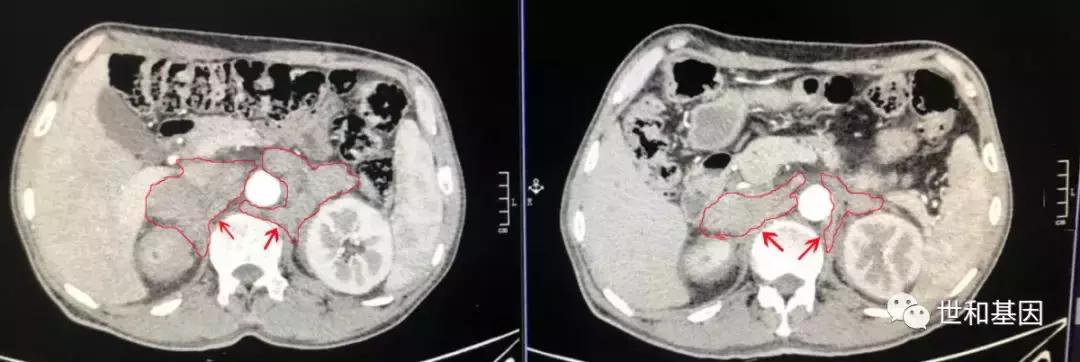

左:治疗前CT(双侧肾上腺区、腹主动脉旁多发转移淋巴结,红色箭头标记)

右:治疗后CT(转移灶明显缩小)